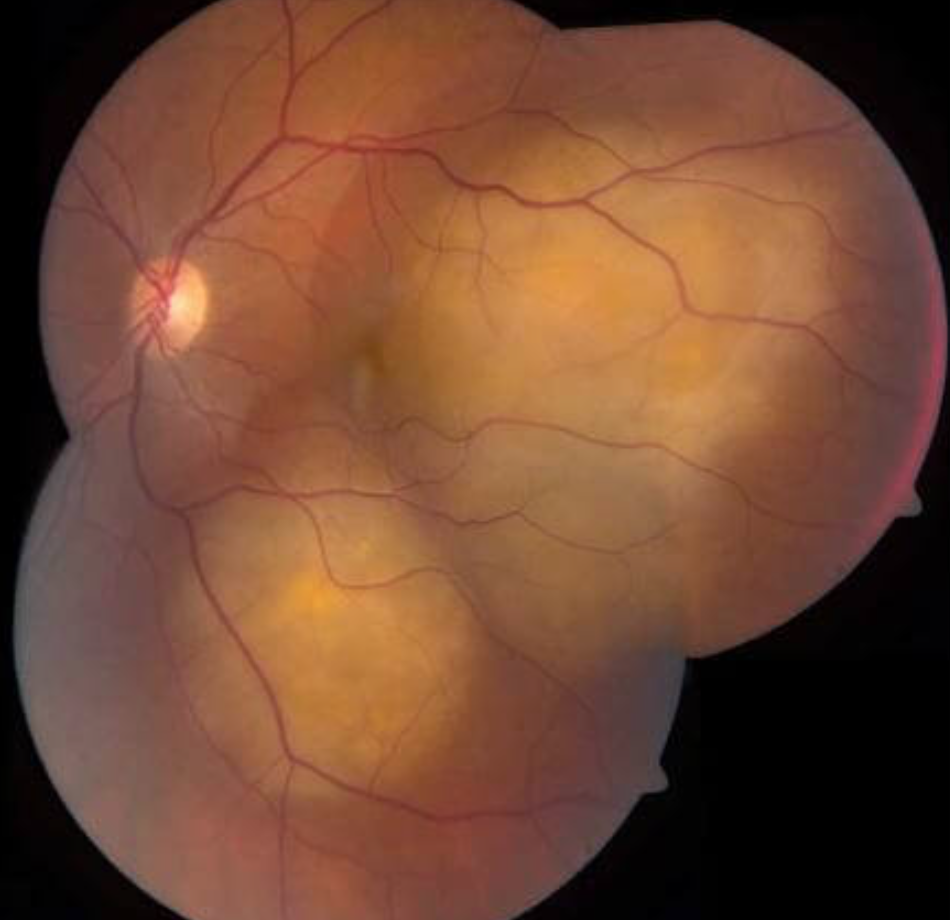

Vascular abnormality → causing leakage of EXUDATES

Exudates become thick + plentiful

Severe enough = cause EXUDATIVE RETINAL DETACHMENT

Multiple clumped lipid exudates

Exudative retinal detachments also possible